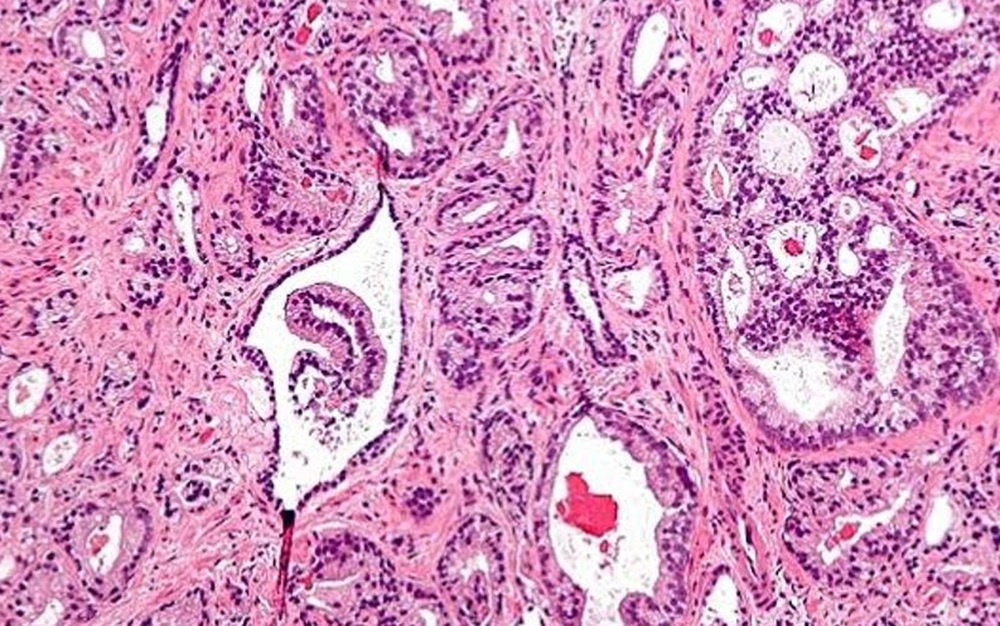

Investigadores del Instituto de Salud Carlos III (ISCIII) han publicado en la revista Frontiers in Cellular Neuroscience un nuevo trabajo que detalla la ultraestructura -término que define la estructura de los organismos que sólo puede ser observada con un microscopio electrónico- de los distintos tipos celulares que componen los organoides cerebrales humanos. Los organoides son 'mini-órganos' desarrollados en laboratorio a partir de células humanas, que imitan la actividad de órganos humanos, en este caso del cerebro, lo que facilita la investigación de enfermedades y la búsqueda de posibles tratamientos.

Gracias a un protocolo desarrollado en el Instituto, publicado este año, el equipo de investigadores ha logrado que los 'minicerebros' generados en laboratorio presenten una gran diversidad de células cerebrales humanas, optimizando la capacidad de asemejarse a cerebros humanos para facilitar las labores de investigación de enfermedades neurológicas. Estos organoides incluyen zonas proliferativas formadas por precursores neurales que se diferencian y migran generando diferentes células cerebrales, como neuronas, astrocitos y oligodendrocitos. Además, presentan otros tipos celulares importantes para el correcto funcionamiento del cerebro humano, como las células microgliales.

Conocer mejor la ultraestructura de los distintos tipos de células presentes en los organoides cerebrales permitirá facilitar el desarrollo de nuevos estudios en torno a los mecanismos que pueden alterar la estructura y la función celular de estos 'minicerebros' de laboratorio, impulsando posibles avances en el desarrollo de organoides más precisos y útiles para la investigación neurológica.